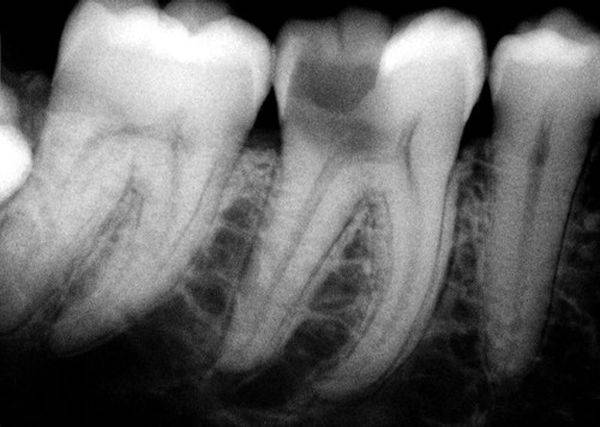

Чтобы диагностировать же пульпит, необходимы иные методики исследования. В их числе электроодонтометрия, позволяющая выявить порога чувствительности к электрическому импульсу у пульпы. Принцип действия этого способа основан на том, что нервные окончания раздражают слабым током. Еще рекомендована термометрия – так именуют диагностические мероприятия, при которых проверяют, как реагирует зуб на соприкосновение с водой разной степени охлаждения либо нагрева. При пульпите возникшая боль сохраняется продолжительное время, невзирая на устранение влияния этого фактора.

При пульпите показатели электроодонтометрии находятся в пределах 15-90 мкА

Рентгенографический снимок пульпитного зуба